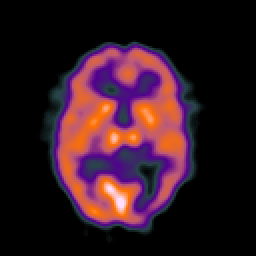

SPECT TC Study #7 -- Slice #29

[Home][Help][Clinical][Tour 1][Tour 2][Tour 3] Slice 29